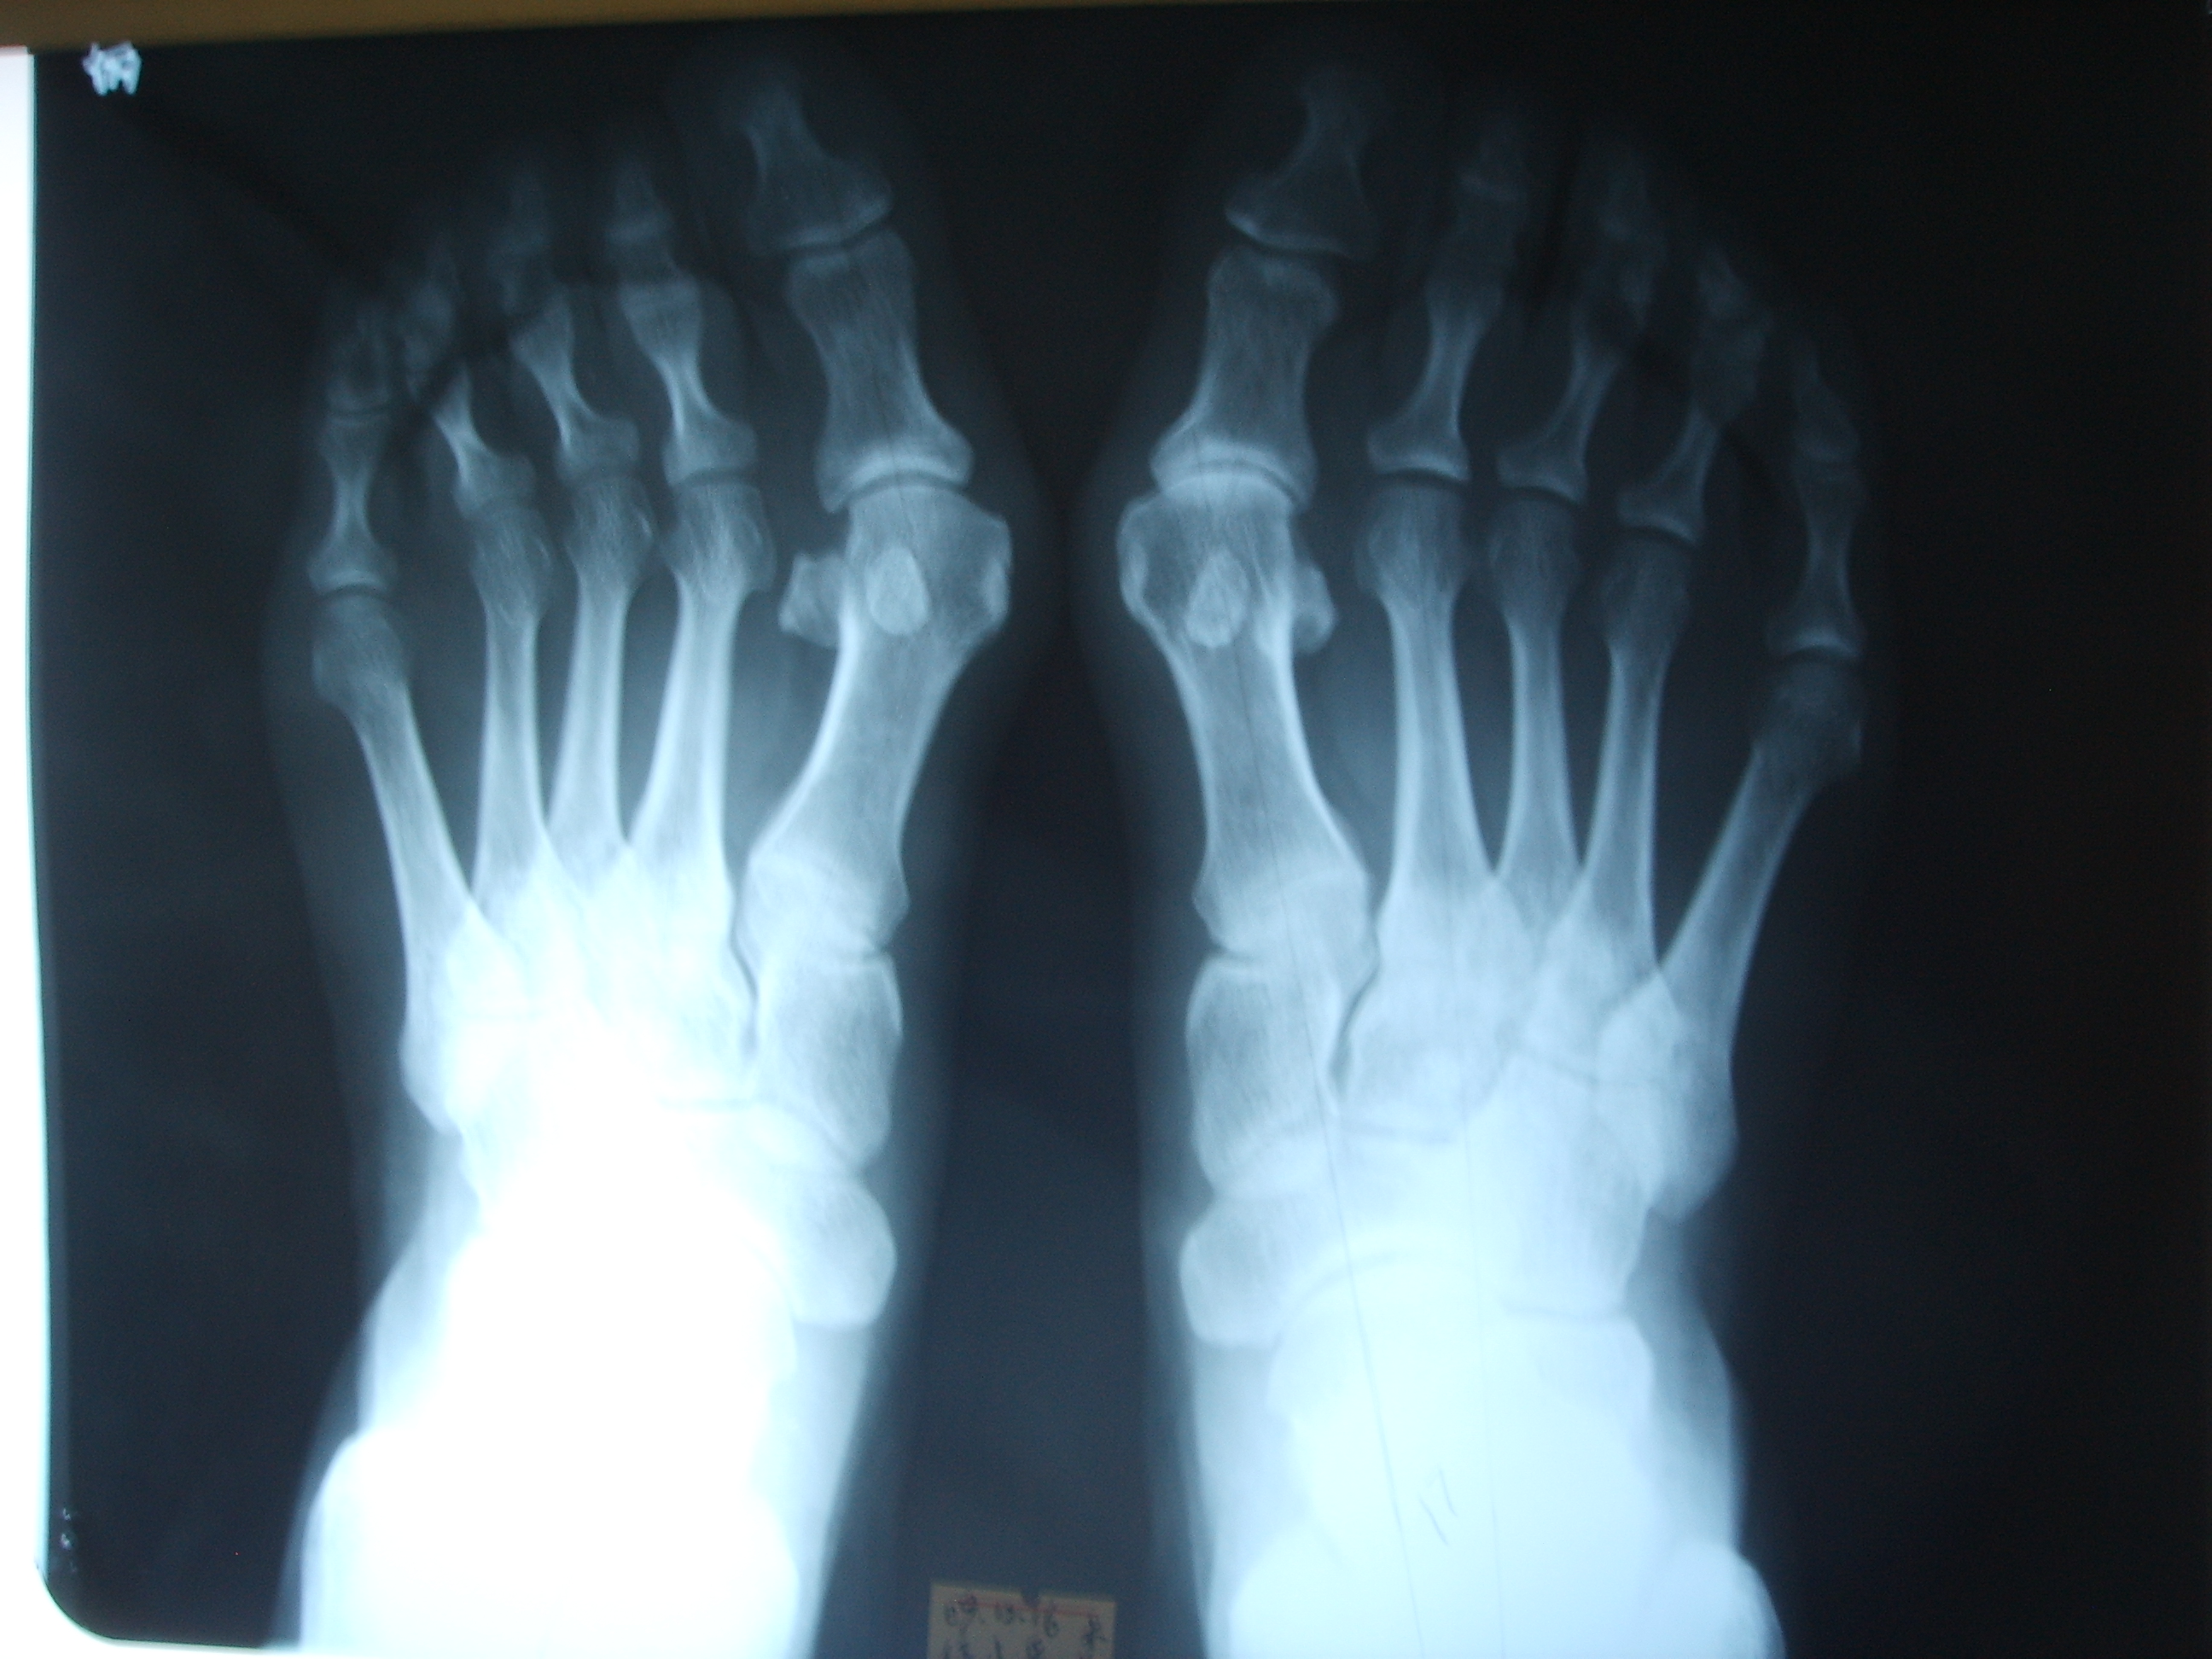

她的左脚第一跖骨有明显的骨赘,第一跖趾关节半脱位,右脚第一跖趾关节脱位没有左脚明显,第一跖骨头下方的籽骨有相对移位,其实她还不算太严重,但是她因为第一跖骨头骨赘明显,所以就会疼痛相对更加严重,拇囊炎也会明显,接下来我们看看她术后的模样。